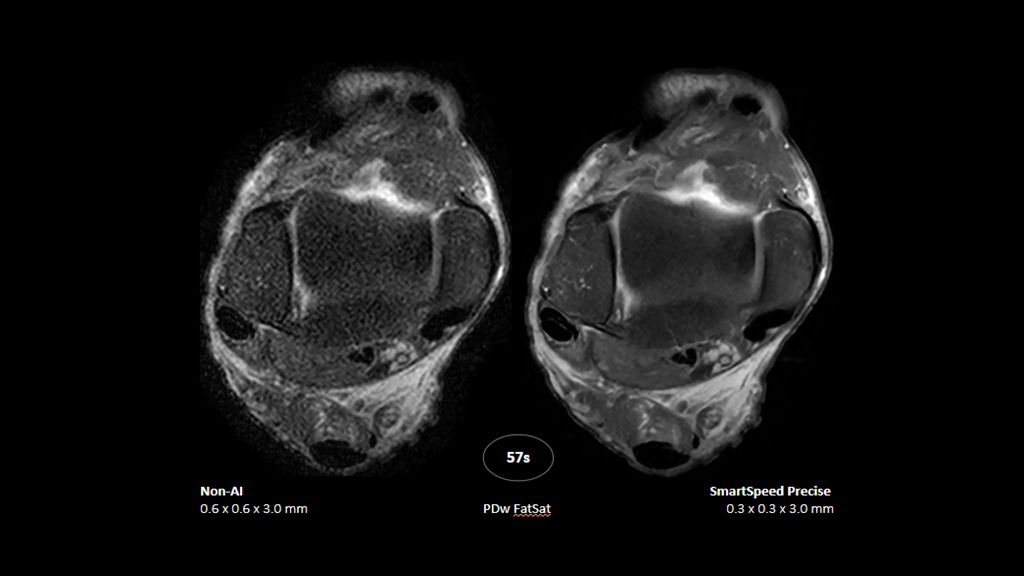

2. Reconstruction technology Compared to conventional (SENSE/ Compressed SENSE, SmartSpeed AI) imaging. Sharpness was evaluated with phantom scanning.